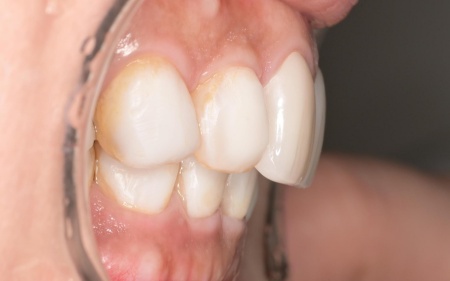

奥歯が噛み合わない状態になったことで、上前歯が前方に押し出され、出っ歯のようになっています。

最初に前歯の位置と噛み合わせの高さを整えるための矯正治療を行い、その後、被せ物による治療で噛み合わせと審美性を回復する方法を提案しました。

まずは、口腔内全体の矯正治療から開始します。

上顎は左上の歯が欠損していたため、左右のバランスを整える目的で、右上の歯(第1小臼歯)を抜きました。

その後、ワイヤー矯正とクローズドコイル(バネの装置)を使ったスピード矯正を行い、前歯を後方に移動させます。